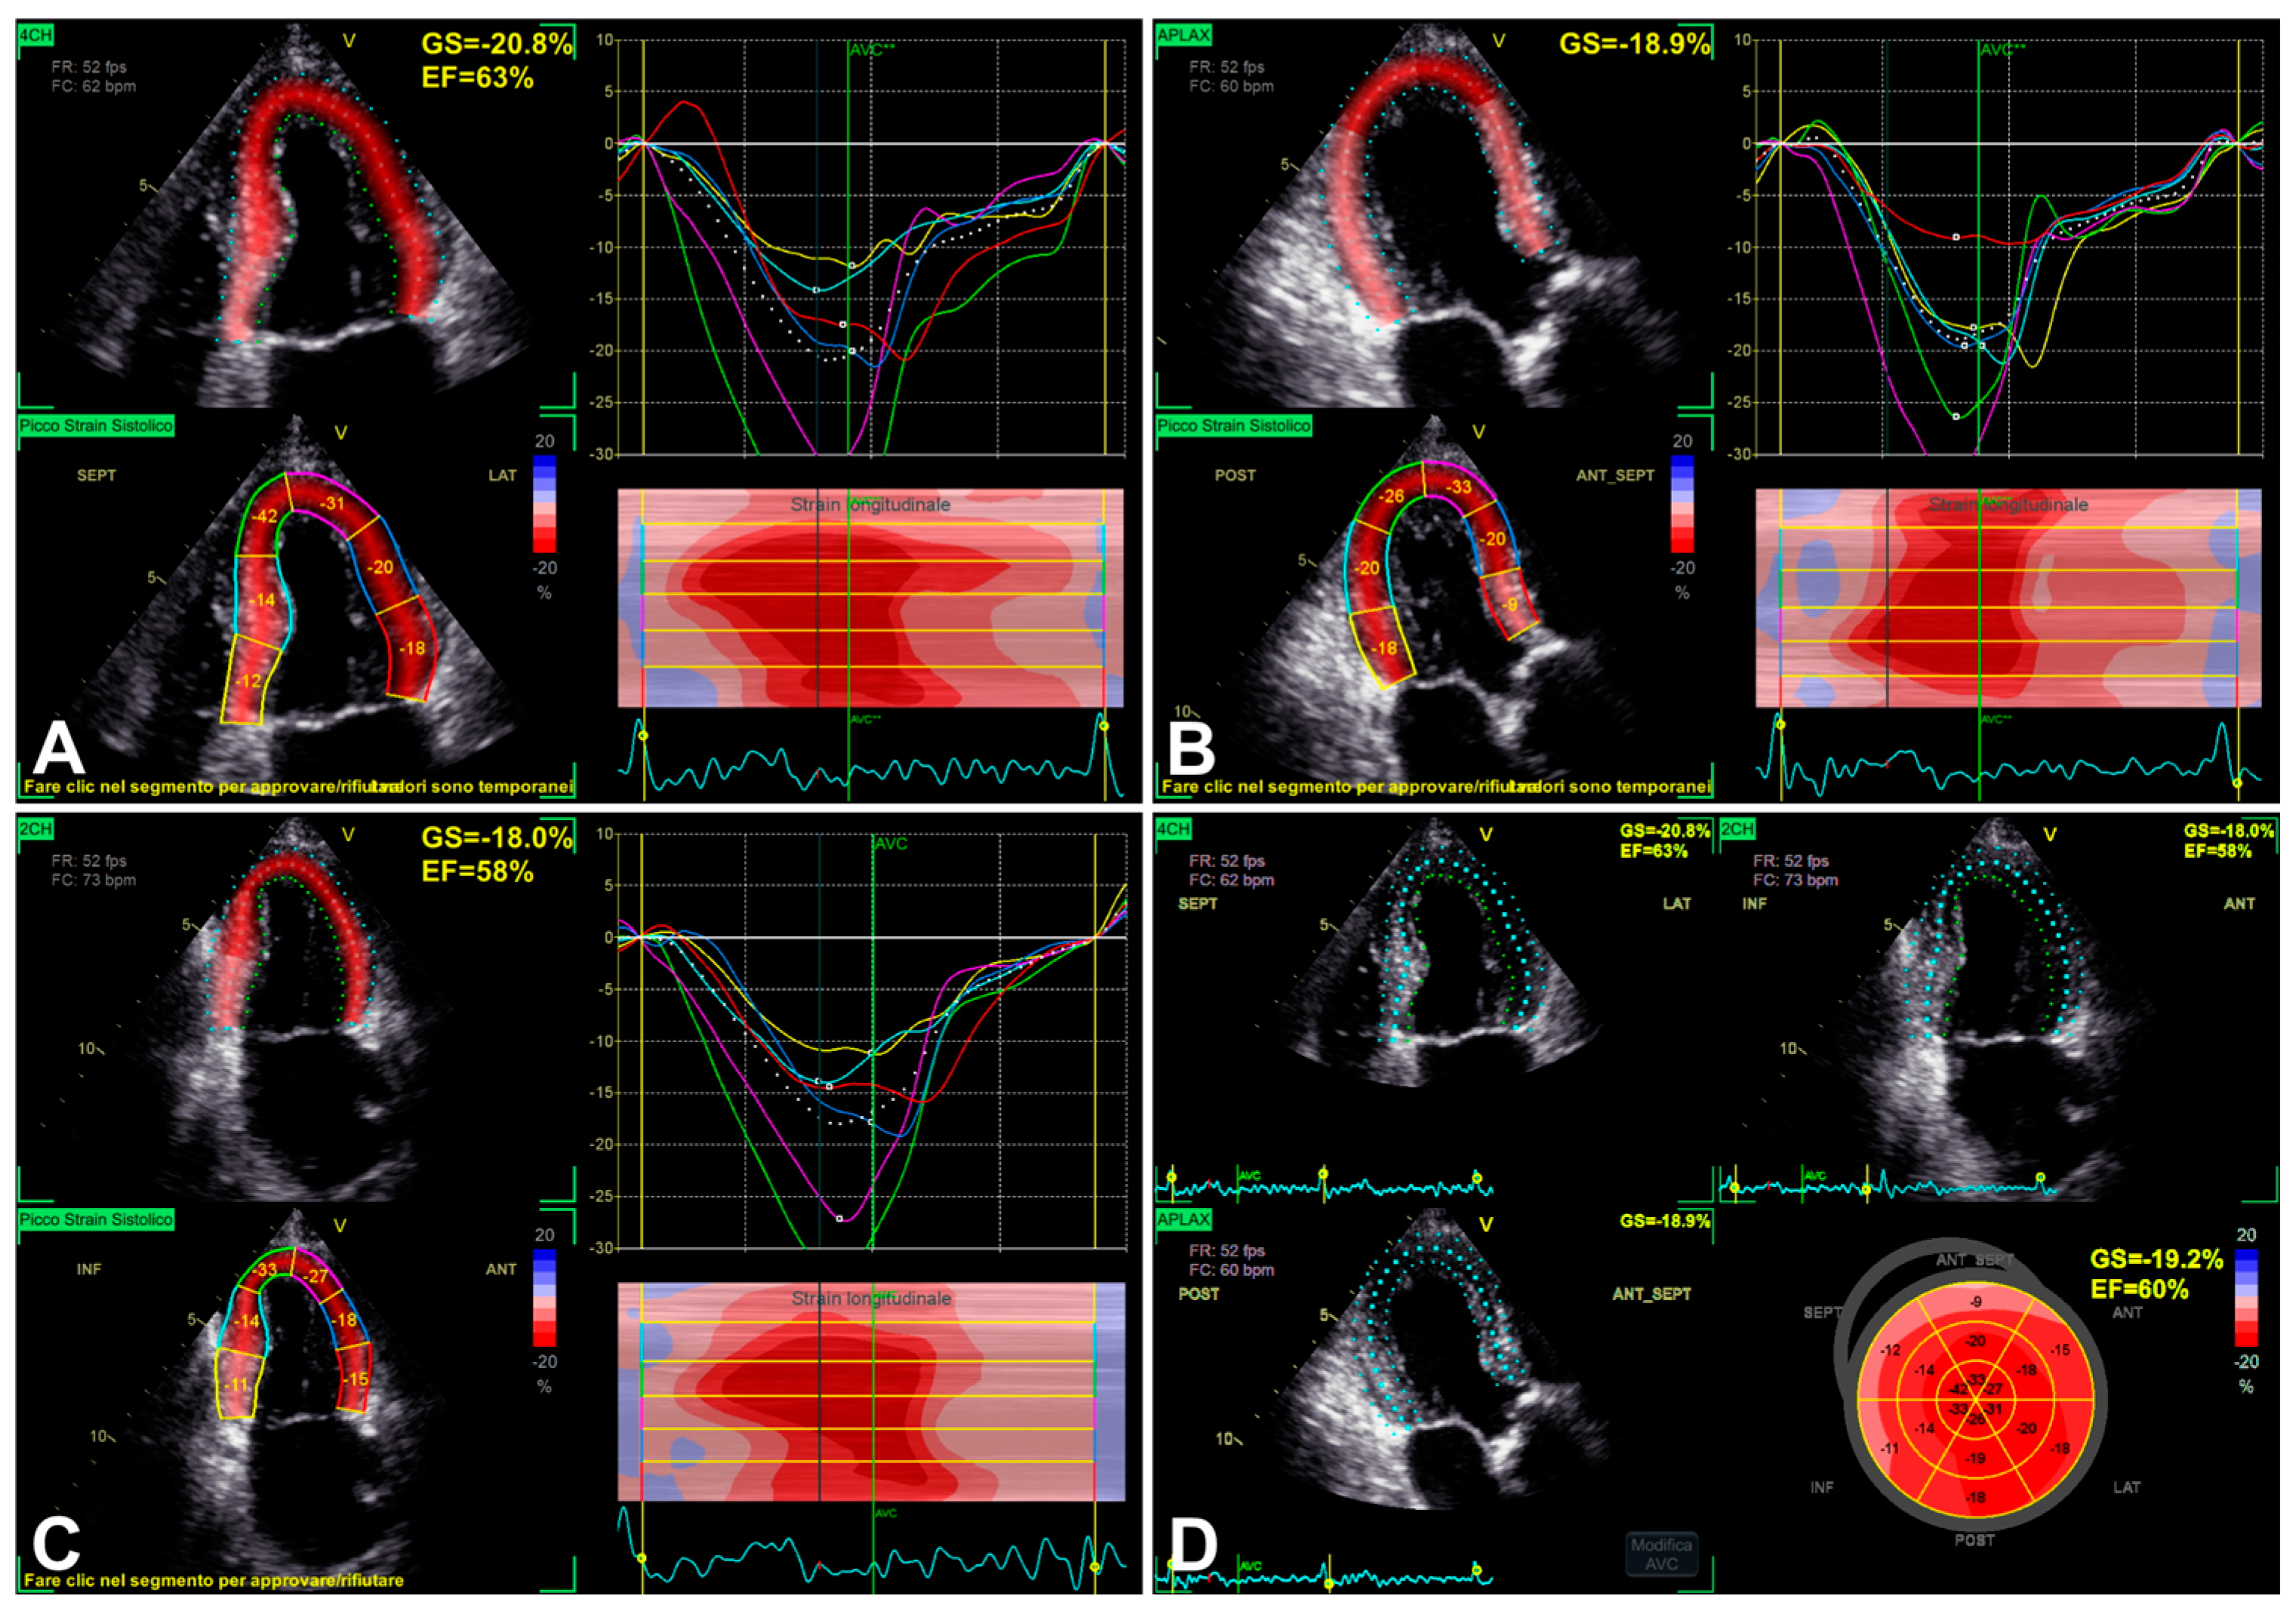

3.1. Left Ventricular Global Longitudinal Strain

| LV GLS | 2D apical 4C, 3C, and 2C views | Probe in apical zone with 4C, 3C, and 2C views | - Prognostic/predictive value. | - Age and load dependency; - Chest shape dependency; - Image quality-related; - Intervendor and intersoftware variability. |